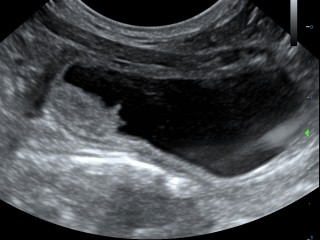

Hieronder zie je een aantal foto's van de buik met achtereenvolgens; blaasontsteking, blaastumor, vroege dracht hond 19 dagen, vergrote eierstok, lever, nier.